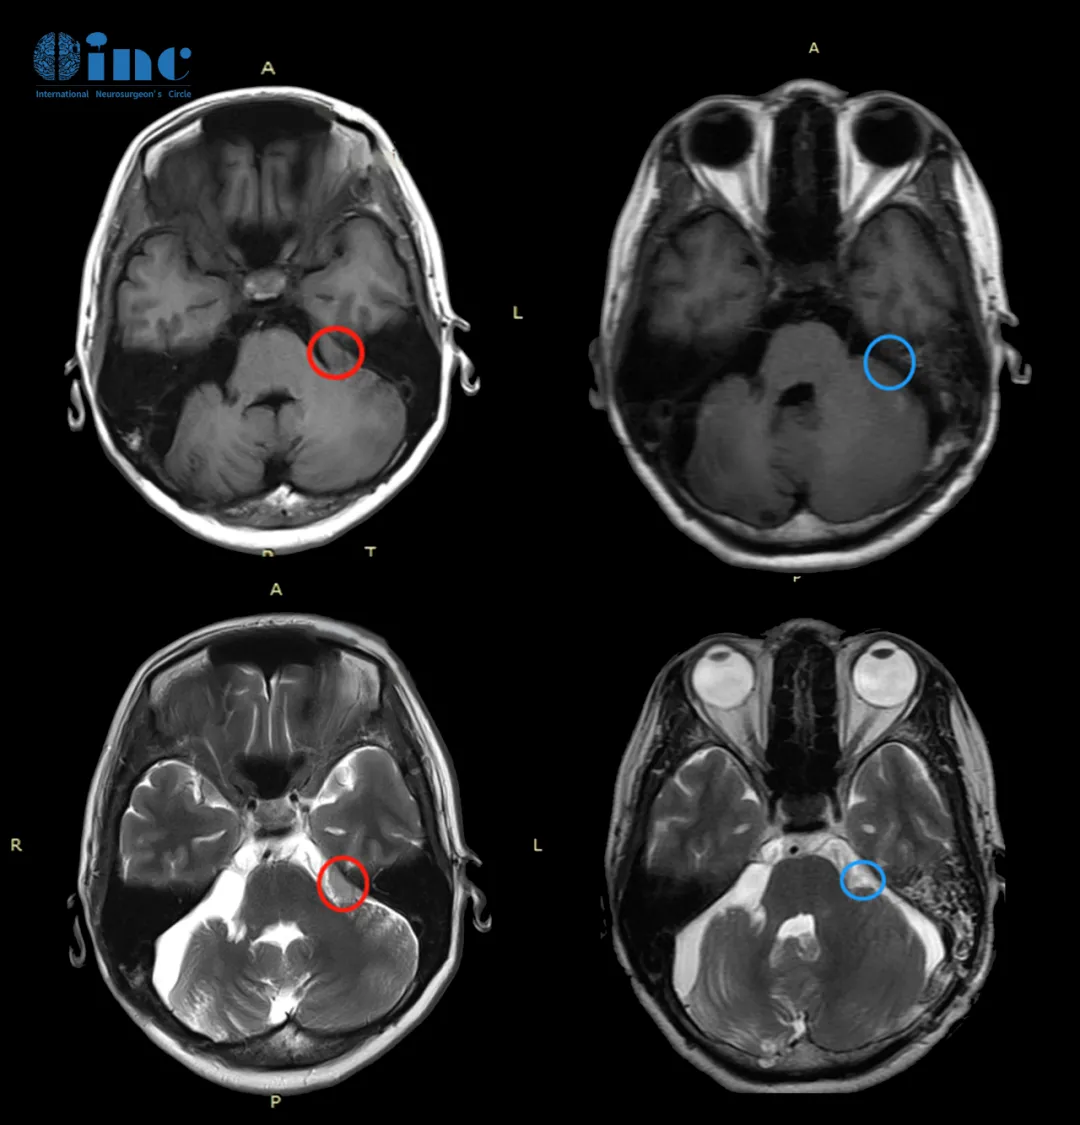

孟女士MR影像

孟女士病情比较特殊,不仅是因为她已经做过一次开颅手术,更是因为她的脑膜瘤长在了CPA桥小脑角区,这是三叉神经、展神经、面神经和听神经等所在之地,并且紧邻脑干延髓、脑桥和小脑。

术前术后影像对比

术后麻醉复苏后,巴教授第一时间到ICU查房。术后第二天,孟女士即转入了普通病房,无新发神经功能损伤,无面瘫,原有听力保留,所有术前症状均有所好转,术后第十天出院。术后1个月视频随访,孟女士状态良好,对巴教授和INC团队多次致谢。

“MRI非常好,没有肿瘤复发或不良副作用。所以情况很好,一切都在按计划进行。建议2年内做一次新的核磁复查。”巴教授在术后2年的随访中回复道。